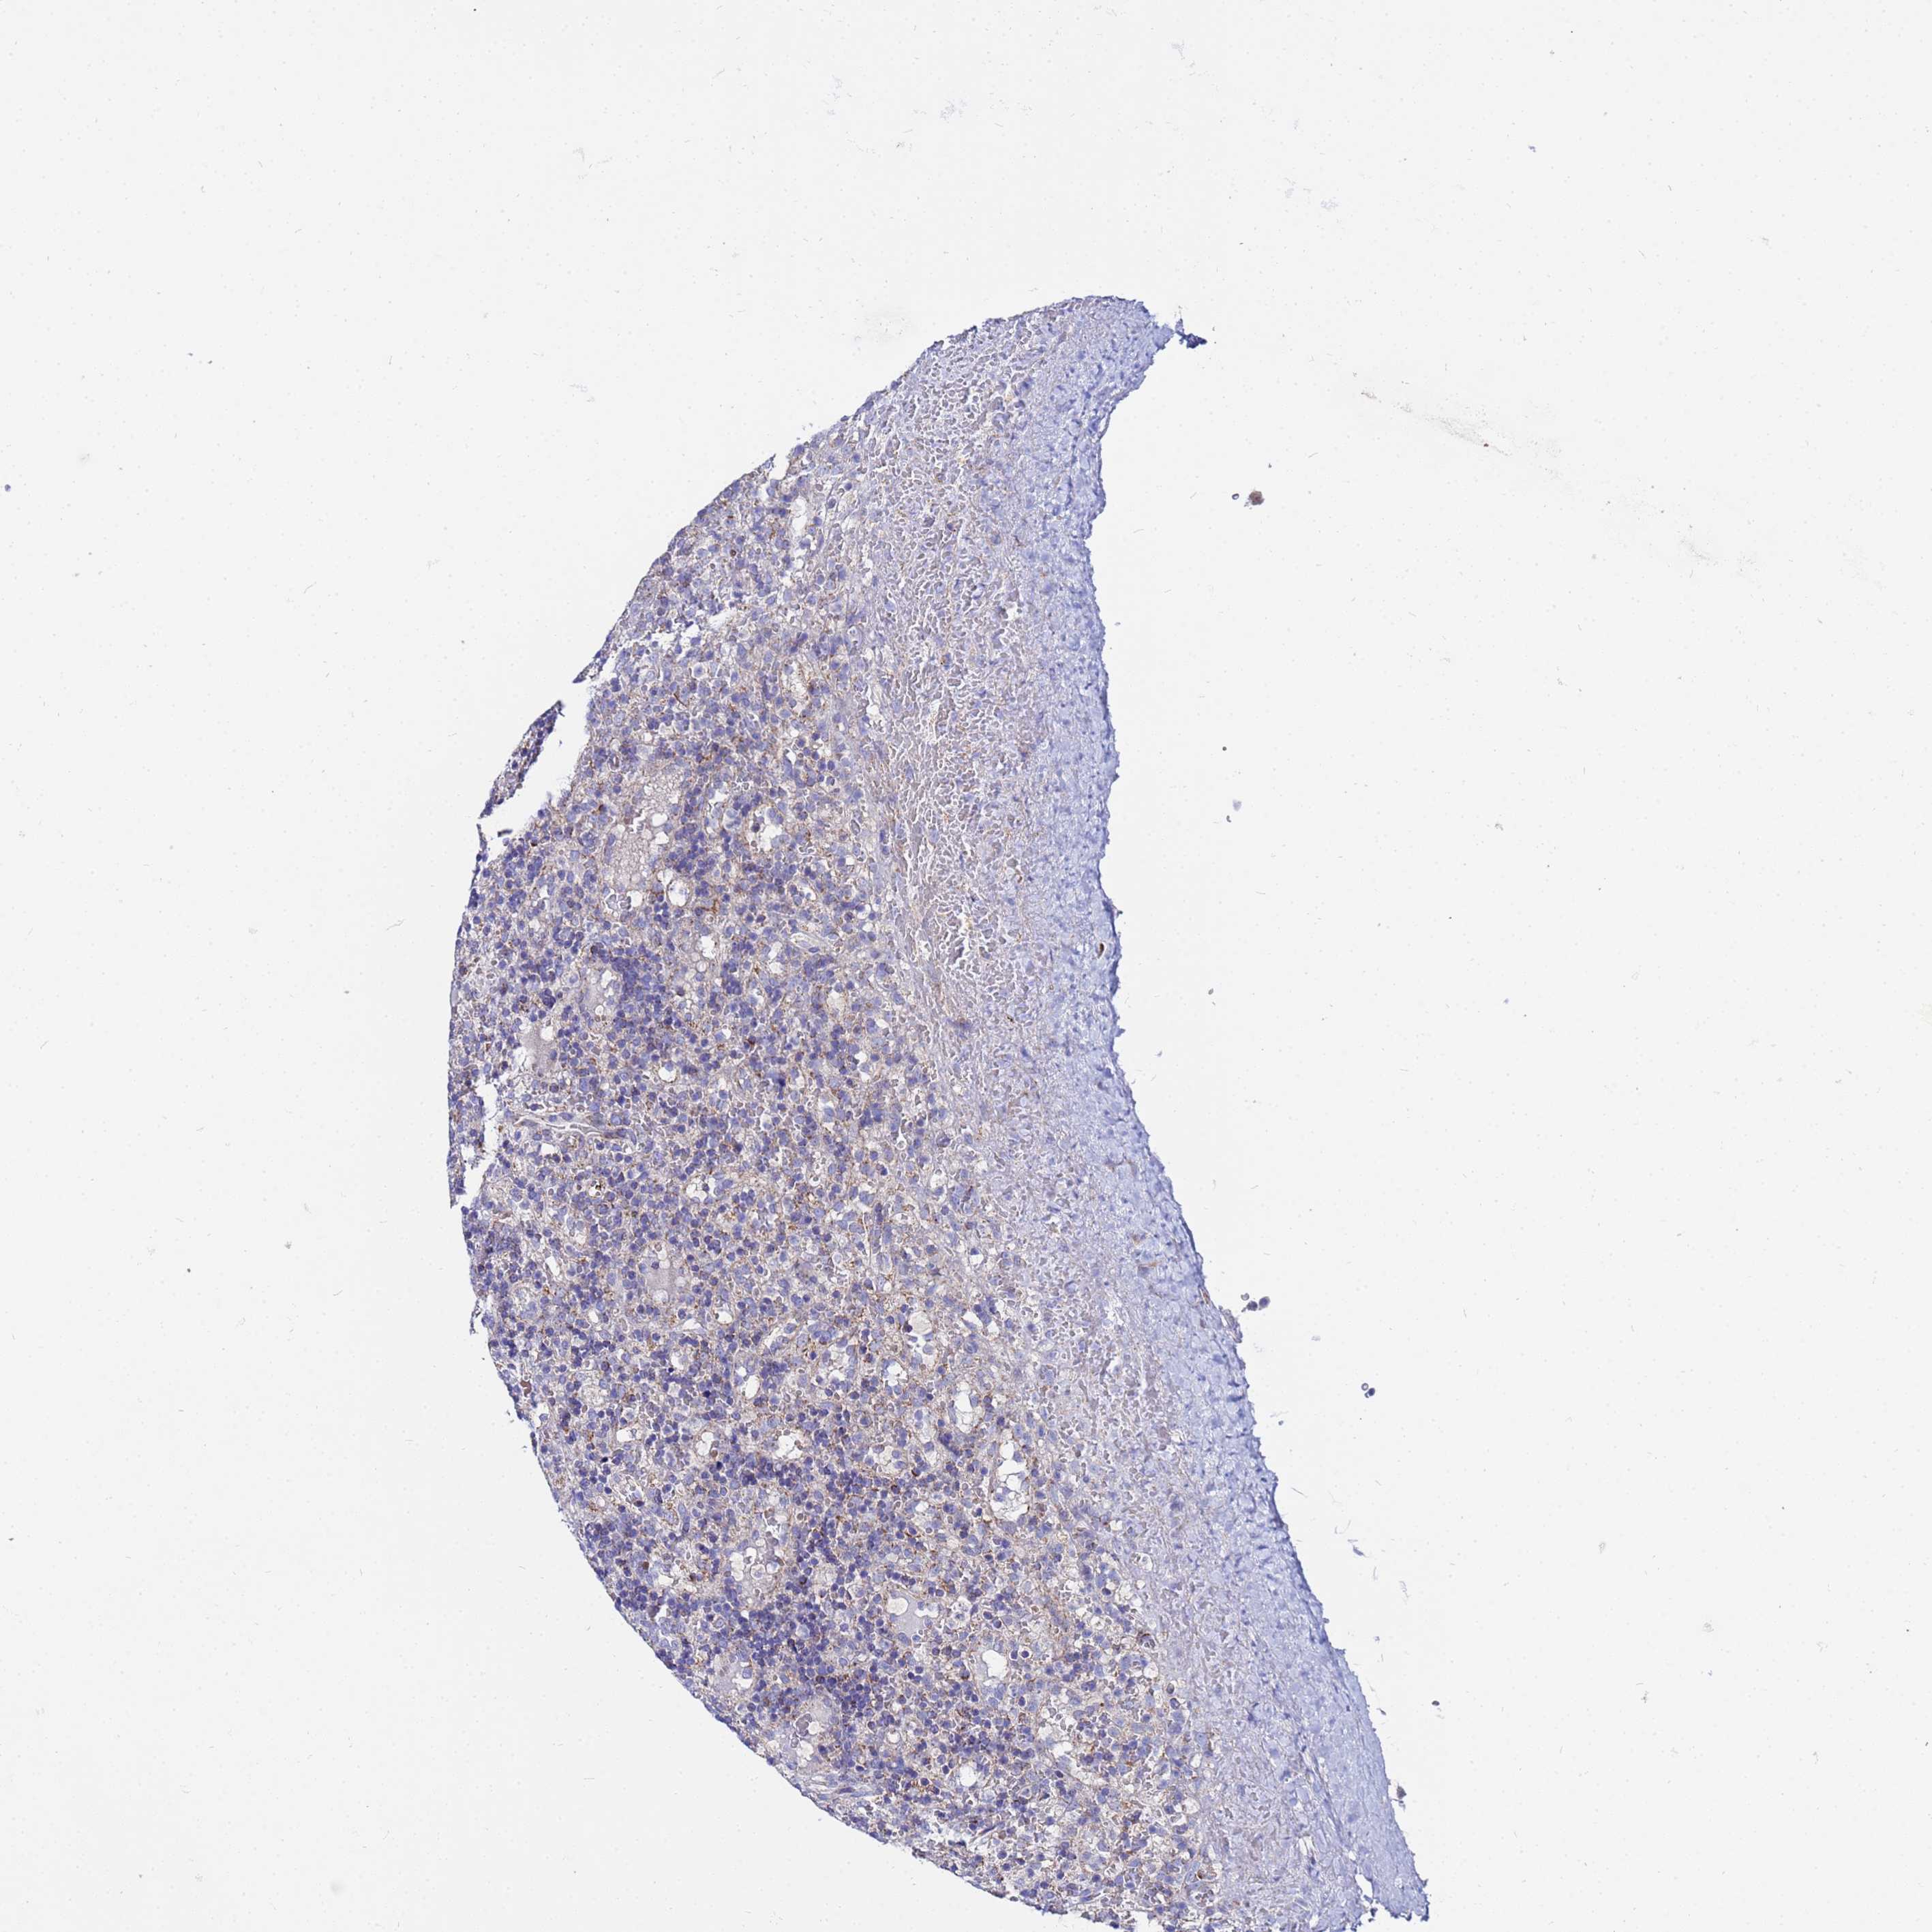

CANCER LYMPHOMA Show tissue menu

LYMPHOMA - Protein expressioni

A mouse-over function shows sample information and annotation data. Click on an image to view it in a full screen mode. Samples can be filtered based on level of antibody staining by selecting one or several of the following categories: high, medium, low and not detected. The assay and annotation is described here.

Each image is clickable and will lead to virtual microscopy that enables deeper exploration of all samples and also displays staining intensity scores, fraction scores and subcellular localization as well as patient and tissue information for each sample.

Antibody HPA042145

Antibody HPA044987

Antibody CAB045971

Antibody CAB045972

Hodgkin's disease, NOS

Malignant lymphoma, non-Hodgkin's type, High grade

Malignant lymphoma, non-Hodgkin's type, Low grade